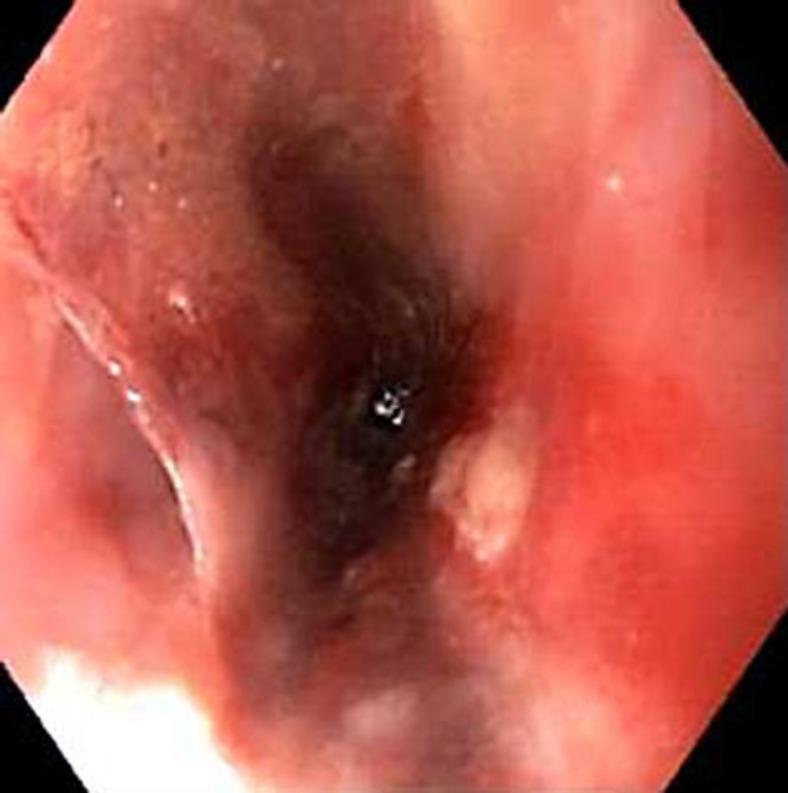

Transesophageal echocardiography (TEE) is a commonly used procedure in patients with suspected endocarditis. A rare but dreadful complication of this procedure is perforation of the esophagus. We report the case of an elderly female with multiple comorbidities, who presented with polyarticular septic arthritis. TEE was performed to rule out endocarditis. Though the standard procedure protocol was followed, she developed esophageal perforation. It was managed with esophageal stenting but she developed multiorgan failure and did not survive. This case highlights the potential of severe morbidity and mortality associated with TEE. Appropriate screening must be done and high-risk individuals must be identified before such procedures are attempted.

经食管超声心动图(TEE)是疑似心内膜炎患者常用的检查方法。该检查罕见但严重的并发症是食管穿孔。我们报告了一例患有多种合并症的老年女性病例,她因多关节感染性关节炎就诊。进行TEE以排除心内膜炎。尽管遵循了标准的操作流程,但她仍发生了食管穿孔。采用食管支架置入术进行治疗,但她出现了多器官功能衰竭,最终未能存活。该病例凸显了TEE相关的严重发病和死亡风险。在尝试此类检查之前,必须进行适当的筛查并识别高危个体。